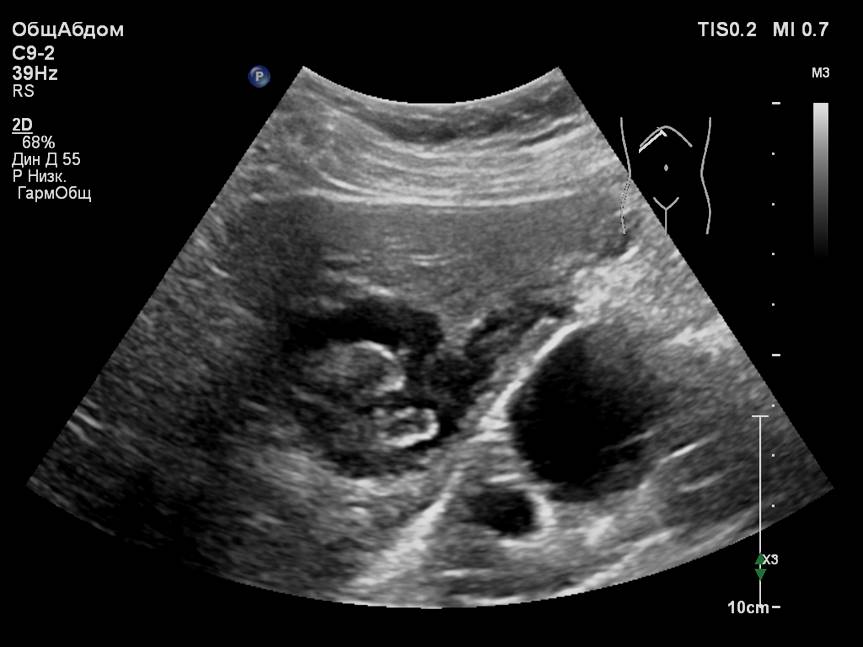

Представлены клинические наблюдения редкого осложнения эхинококкоза печени – прорыва эхинококковой кисты в желчные протоки. Осложнение стало причиной обструкции желчных протоков, механической желтухи и холангита. Освещены этапы диагностики, роль УЗИ в выявлении осложнений эхинококкоза печени, рассмотрены способы минимально инвазивного лечения с применением эндоскопических и чрескожных технологий под контролем лучевых методов.